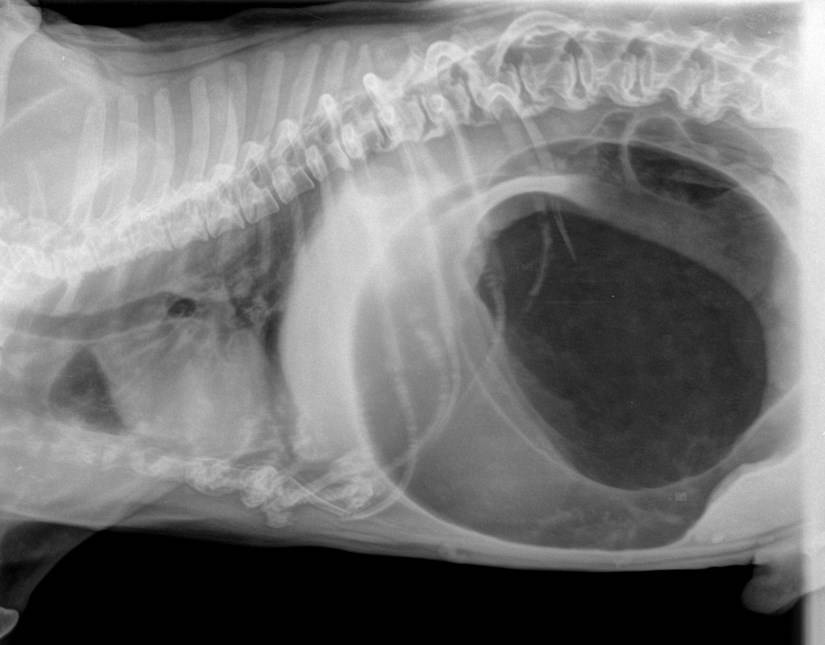

Рентгенография желудка собаки

В отношении щенков распространенной причиной является попадание в желудок инородных тел. Если пес съел часть игрушки или любой другой предмет, понадобится проводить рентгенографию. На фоне этого в организме может начаться интоксикация, угнетающая работу центральной нервной системы. Помимо икоты щенка может беспокоить синюшность слизистых оболочек, рвота, слюнотечение, слабость и тремор.